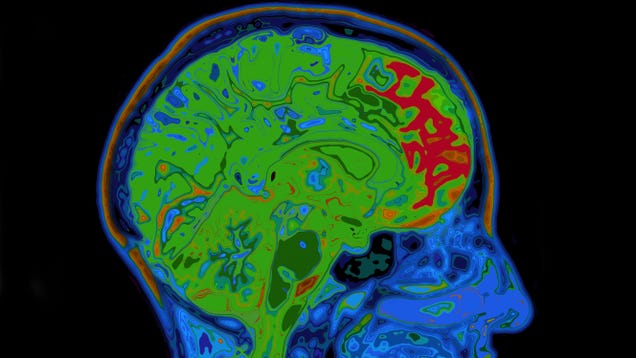

New clinical trial data released by Eli Lilly on Wednesday has provided the most promising results of any potential Alzheimer’s disease treatment yet. In a randomized, double-blinded, controlled phase III trial, the experimental drug donanemab significantly slowed cognitive decline in patients compared to placebo,…

Source: Gizmodo – New Trial Data Is Strongest Yet for Any Experimental Alzheimer’s Drug